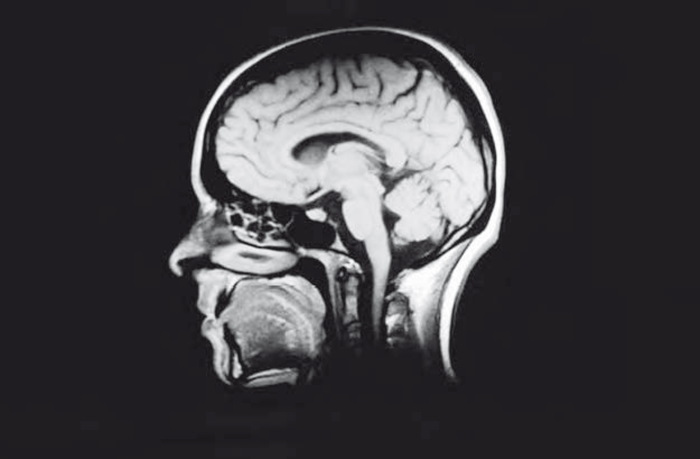

Иллюстрация к книге — Сознание за пределами жизни. Наука о жизни после смерти [i_019.jpg]

МРТ мозг

В настоящее время методы научных исследований, по-видимому, неспособны в точности изучать нейронные процессы, связанные с нашим опытом сознания. Если изменяющееся взаимодействие между крупными группами нейронов действительно является нейронным коррелятом сознания, наши нынешние методы исследований непригодны для такой задачи, как запечатление этого процесса. Даже самые современные и детальные сканы фМРТ показывают нам не более чем физическую основу процесса наблюдения или осознания и никак не объясняют, что именно происходит в нашем мозге. Кроме того, сканы фМРТ ничего не говорят о содержании наших мыслей и чувств. Поэтому вызывает тревогу то, что исследования с применением фМРТ побудили некоторых ученых прослеживать причинно-следственную связь между некоторыми функциями мозга и специфическими умственными процессами [3].